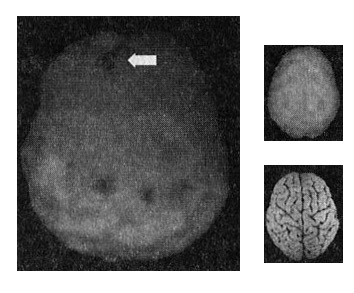

Они все-таки поехали кататься на квадроциклах. Джей ехал на скорости 40 миль в час, когда переднее колесо налетело на скрытый в песке булыжник. На всей скорости Джей вылетел из машины. С какой скоростью двигался его мозг, пока он летел в воздухе? 40 миль в час. Он врезался в песок головой, одетой в шлем, и мозг за мгновения перешел от скорости 40 миль в час до нулевой. Как вы думаете, что происходило внутри его черепа? Мозг колыхался туда и сюда. Ненадолго Джей потерял сознание. Учитывая, что он уже начал встречаться с моей дочерью, у меня имелся скан его мозга, сделанный в начале их отношений (в моей семье есть такое правило: хотите встречаться с моими дочерьми — сделайте томограмму мозга). Через два месяца после происшествия томограмма показала темные провалы в лобной коре (рис. 10.1 и 10.2).

Мозг Джея

Рис. 10.1 До аварии

Здоровая активность

Рис. 10.2 После аварии

Повреждения в право части коры лобных долей (отмечено стрелкой)

Наконец-то до обоих дошло, насколько я был прав. Защита мозга от травмы — это залог полноценной личности.